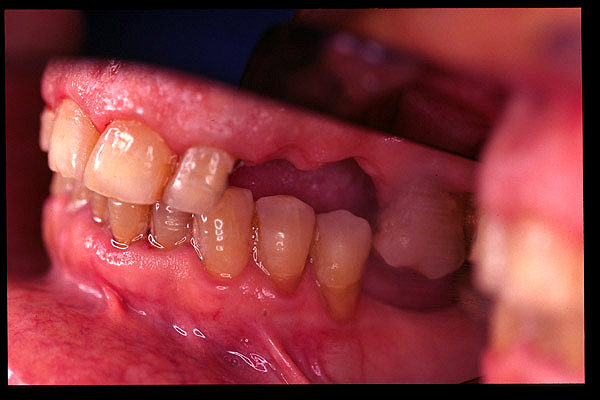

CM Extrusión de molar superior y premolares inferiores por falta de antagonista